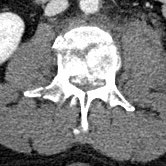

IM-0005-0083 L-spine.jpgIM-0003-0038 L3.jpgIM-0003-0031 L2.jpg

The fly-through doesn’t show the spinal injury very well, so here are some 2-D sections. The left panel is a section of my lumbar spine viewed from my left side; note the obviously smashed L3 vertebra. The middle panel is a top-view slide of L3, and the right panel is healthy L2 (the vertebra immediately above) for comparison.